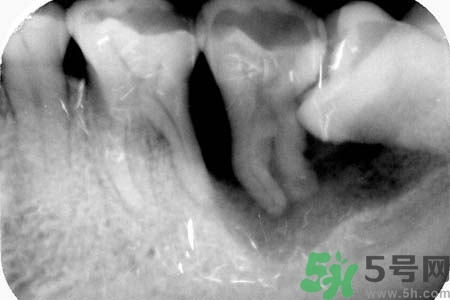

不少人長了智齒后拍片子顯示牙齒橫著在長,出血這種情況的時候該怎么辦?智齒橫著長一定要了拔嗎?關于智齒橫著長怎么辦?智齒橫著長一定要拔了嗎?智齒不疼需要拔嗎?小編為您一一解答。

如果發(fā)現(xiàn)自己的智齒橫著長了,為了不讓智齒阻生引起其他的危害,我們一定要盡快把橫著長的智齒拔除,而且不需要鑲牙,拔掉之后有助于身體健康,還可以保護附近其他牙齒。但是,我們還要重視一點,拔智齒是一種牙科門診手術,要求醫(yī)生的技術水平要比較高,因為橫生的智齒,拔除的時候難度更大,首先要將黏膜切開,去骨之后才可以拔除的,這不是普通的牙醫(yī)可以把握好的。所以,小編在此提醒各位患者,務必選擇正規(guī)的牙科醫(yī)院,由專業(yè)的牙科醫(yī)生進行拔除手術。

智齒橫著長在拔除的時候需要遵循一些原則。正常情況下,生長情況沒有出現(xiàn)異常的智齒盡量要保留下來,不要隨便進行拔除。特別是那些生長了很多年的智齒。只有當智齒非正常生長,出現(xiàn)一些臨床癥狀的時候,才有拔除的需要。而且,在進行拔除手術之前,一定要先拍攝牙片,確定智齒生長異常再進行拔除。還有,發(fā)炎的智齒也必須要拔掉。但是如果炎癥消退,而且沒有出現(xiàn)復發(fā)的話,也可以不拔。

智齒橫著長具有很大的危害,它會擠壓附近的牙齒,嚴重時會導致整排的牙齒看起來都不整齊。而且還會影響到患者的咀嚼功能。智齒阻生跟前牙間會容易殘留食物殘渣,積累細菌,引發(fā)齲齒或冠周炎。如果一旦出現(xiàn)冠周炎就會反復地發(fā)作。智齒橫著長還會影響牙齒的咬合,長期下來更會引發(fā)下頜疼痛、夜磨牙等。很多20多歲左右的年輕人,總是覺得牙齒疼痛,去醫(yī)院檢查都會發(fā)現(xiàn)是因為智齒橫著長。但是智齒橫著長很難察覺,通常都是是引發(fā)了疼痛,患者才會開始所察覺。

必須拔除,不然的話容易導致第7牙齲齒,智齒拔除不會導致其他牙齒松動移位。在臨床上看起來,大多數(shù)的人應該都有智齒,所以可以自己照鏡子看看由中線算起的上下左右是不是都有第八顆牙?長的好不好?正不正?是不是常常會發(fā)炎疼痛?而且算完之后,不管有沒有第八顆牙,在定期檢查時都應請牙醫(yī)師確認一下,如果是天生缺牙時倒還值得慶賀,因為一切沒事,如果不幸發(fā)生了長不出來的情形,那只好請牙醫(yī)師盡早將它拔除。